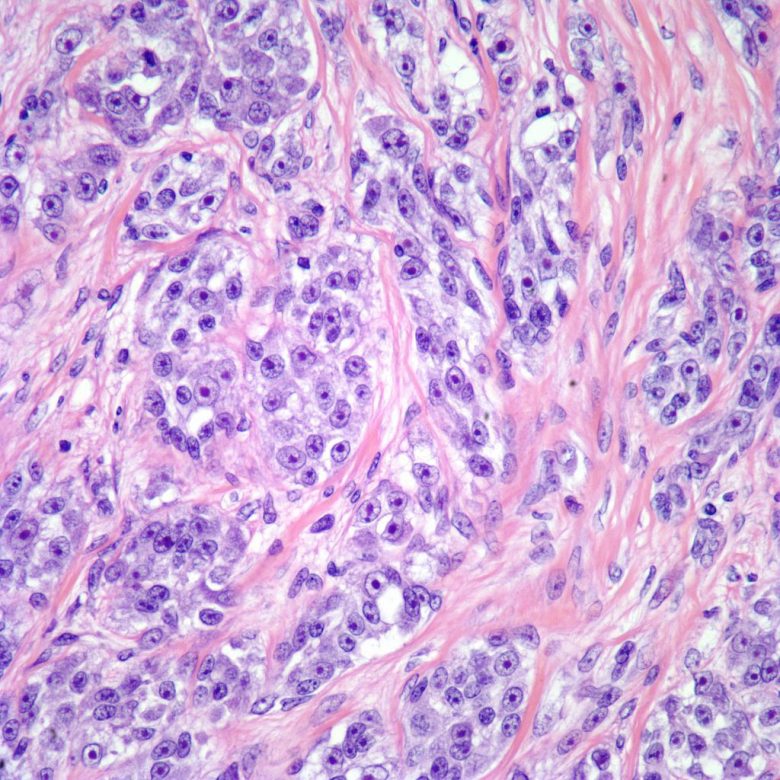

Prostate cancer

“Prostate cancer is the most common cancer and the second leading cause of cancer death among men in the United States. Prostate cancer usually grows very slowly, and finding and treating it before symptoms occur may not improve men’s health or help them live longer.”